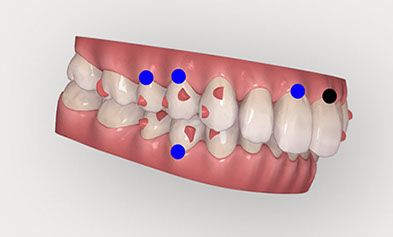

精密検査 (来院)¥60,000(税抜) 2回のカウンセリング後、治療を希望される場合には、治療計画を立てるために必要な精密検査を受けていただきます。 CADIAXという検査機器による下顎運動の測定やセファロレントゲン撮影などの画像検査が含まれます。 カウンセリング 3回目 (来院またはオンライン) 無料/60分 精密検査から診断がなされ、診断に基づいた治療計画を立案します。治療計画はアライン・テクノロジー社が開発した3D治療計画ソフトウェア「クリンチェック」を使います。 3D治療計画では、予測される最終的な歯並び(治療結果の保証ではありません)が示されるほか、おおよその治療期間も提示されます。 3回のカウンセリングにより、歯科医師が考えるゴールと患者さんの考えるゴールについてのすり合わせを行い治療方法を決定します。